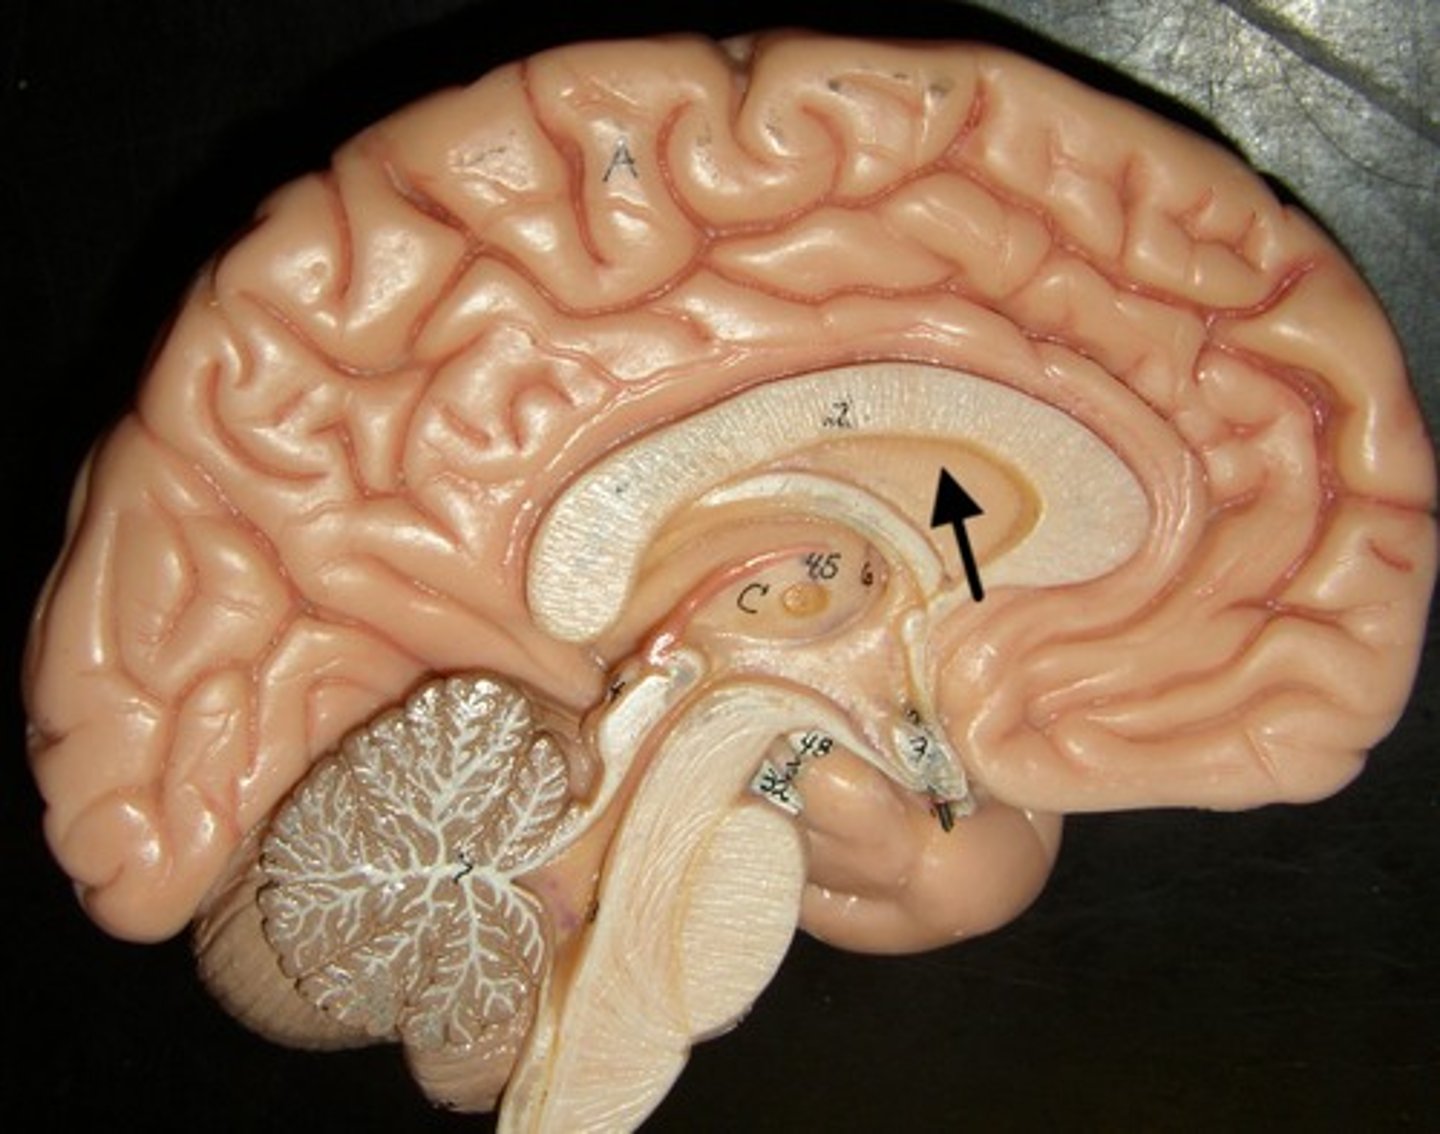

lateral ventricles

third ventricle

fourth ventricle

interventricular foramen

connects lateral ventricles to third ventricle

cerebral aqueduct

connects the third and fourth ventricles

choroid plexus

on the floor of all the ventricles, produces CSF

corpus callosum

septum pellucidum

membrane that separates lateral ventricles